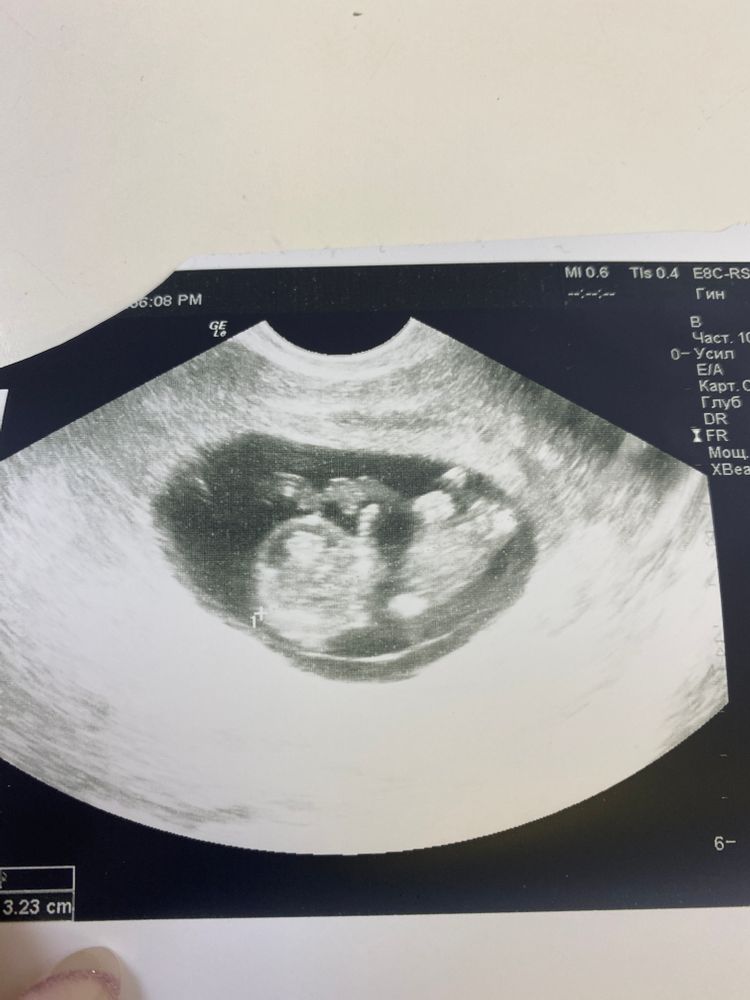

Девочки привет! Решила сегодня сбегать на узи так как за эту неделю со мной много чего не очень хорошего происходило! ( давление то падало, то повышалось было дикое носовое кровотечение, так же очень сильно резал живот по всей окружности и желудок стоял! А малышок мой себя чувствует хорошо, чему я очень рада! Девочки теперь поняла одно ☝️ самое главное Без паникииииии! Малыша сегодня описали как плод, чему я очень рада!❤️ Боженька помоги всем нам мечтающим стать мамой!🙏🙏🙏🙏

Уже человечек😍Дай вам Господи! Ттт, пусть растёт малыш, пусть порадует своим криком мамулю через 30 неделек 🙏🏼 да будет так🤞🏼

Вай какая ляля хорошенькая!🥰 Ттт на вас. Растите здоровенькие и лёгкой вам беременности 🤗